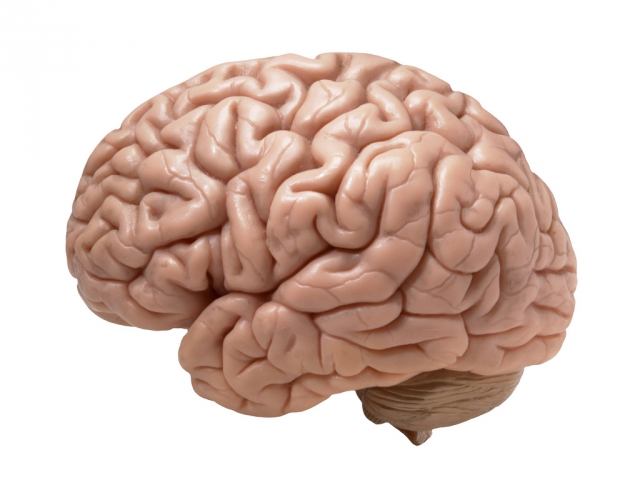

اعراض نقص الاکسجین في الدماغ من المشاكل الصحية التي قد تواجه الكثيرين في تلك الأيام، حيث يعتبر الأكسجين أحد العوامل الهامة التي لا يستطيع أي كائن حي العيش بدونه، وقد يتسبب نقصه عند الشخص تتوقف الدماغ لديه.

اعراض نقص الاکسجین في الدماغ

الحاجة للأكسجين هو المصطلح المسمى بعوز الأكسجين ويطلق عليه نقص أكسجة الدم _ hypoxia حيث يحدث ذلك عند نقص كميات الأكسجين التي يحصل عليها جسم الشخص، ولنقص الأكسجين أعراض وإشارات منها:

نقص تروية الدماغ

من المهم والضروري عند مراعاة الحالة الصحية لأي شخص أن نهتم بطبيعة الحالة التي عليها، وأن نعرف عند نقص وجود الأكسجين هل الأمر اعراض نقص الاکسجین في الدماغ؟ وما هي نسب وصول الأكسجين للدم؟ وهل الدماغ تعمل بشكل طبيعي أم أن هناك قصور في عملها؟ والعمل على علاج مشاكلها وتعرف عملية نقص تروية الدماغ بأنها المنطقة المحرومة من الدم وبالتالي من الاكسجين، والتي من مضاعفاتها: